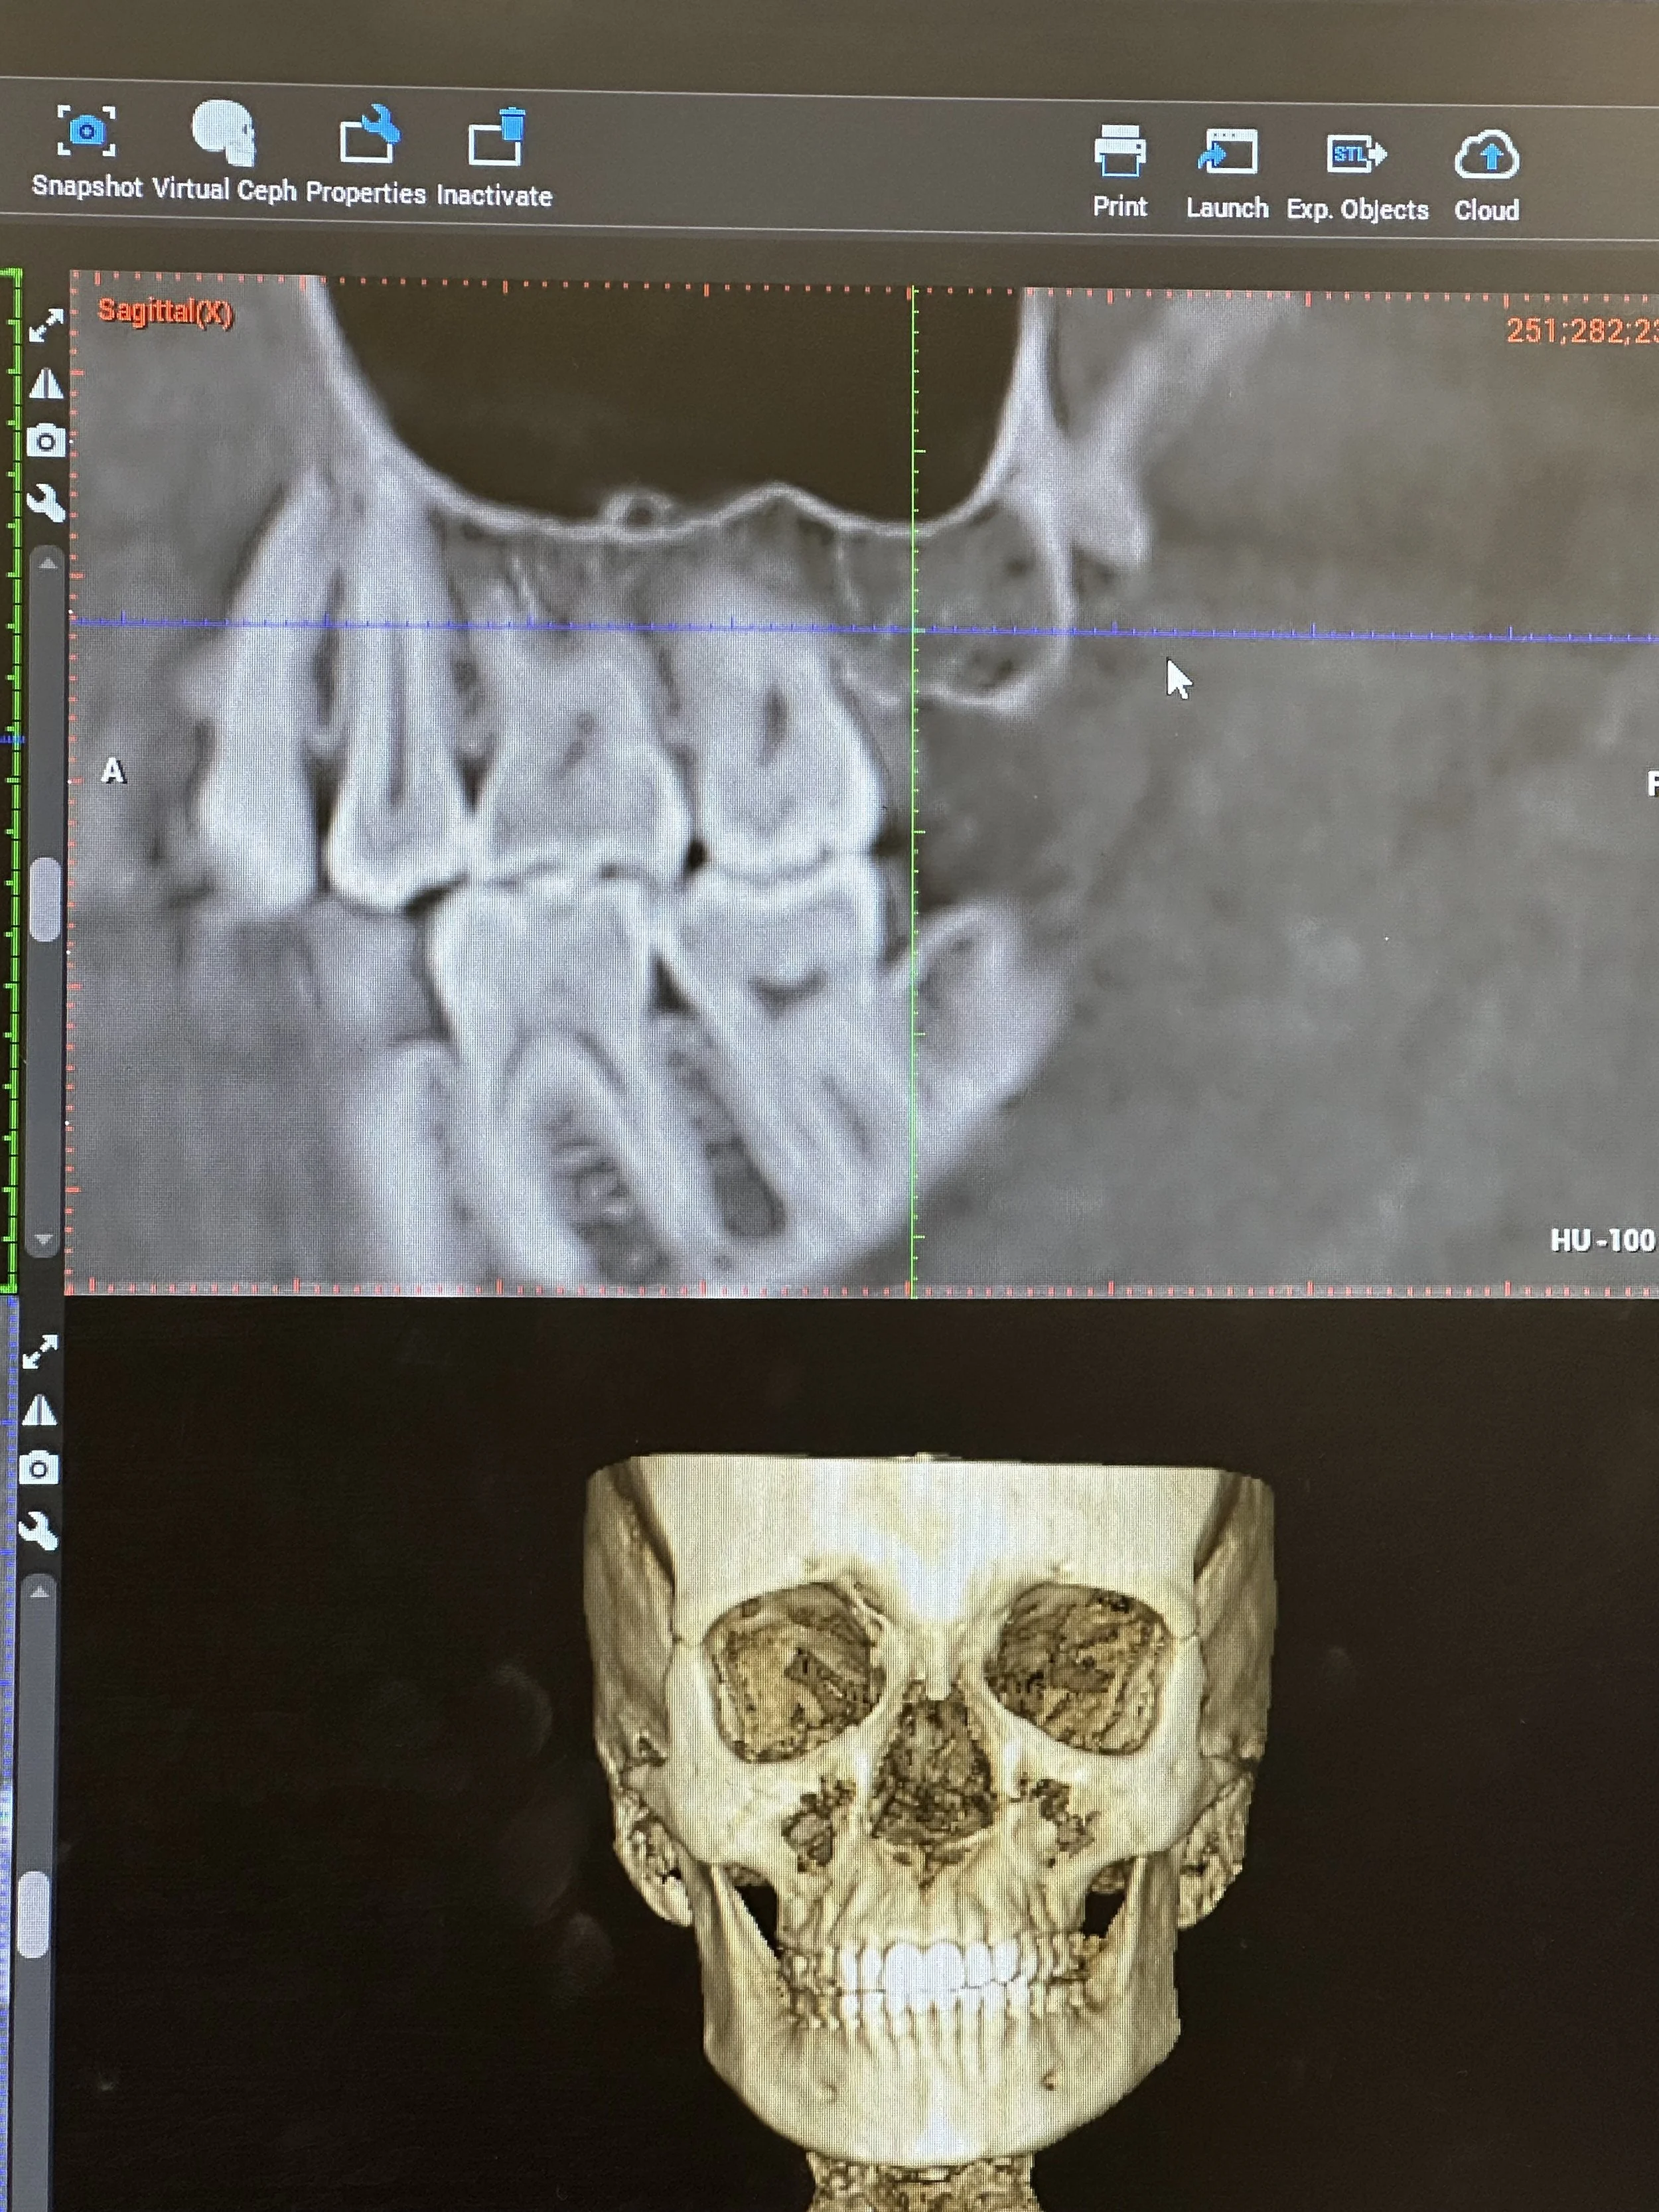

Conebeam CT scan confirmed hole in the bones of all four of my wisdom teeth extraction sites by my biological dentist.

Top image indicates the cavitation encapsulated by scar tissue, which closes the area off from the rest of the body as a protective measure. This is the extraction site of Tooth 1 (upper right, back).

After confirming some things for me on my cone beam images (which were used to confirm the cavitations six months ago), like the severity of the situation and the nerve damage risk associated with surgery, I felt comfortable to lay back and let my dentist dig into the back of my mouth with one of his many prodding, sharp tools (unsure of exactly which tool, because I closed my eyes 🫣). Straightaway, he began hacking through gum tissue searching for a spot on the bone cap - the only bone that did grow back after wisdom teeth, a thin layer across the topthat he could penetrate. This would give him access to the holes left in my jaw where teeth once were all those years ago - these holes are what are known as a “cavitations.”

He started with the top cavitation: found the hole through a bone cap and some scarred tissue that had begun to wall off the cavitation in an attempt to protect my body from it. By walling it off, like your body does when you get a splinter, it is prevented from access to blood supply. Once he was in, he inserted ozone treatment to clean the bacteria and encourage angiogenesis - the growth of new blood vessels in an area. Blood brings nutrients and oxygen to the area, which is how it heals and regrows. He mentioned that there was no blood when he cut into it initially, and that to get bleeding he had to utilize the ozone. After it sat in the cavitation for a few minutes, blood started to arrive.

Just to give you an idea of what’s possible, look at my experience: there were bone fragments hanging down in a dead hole in my upper jaw, like stalactites in a cave, with no blood supply, surrounded by scar tissue to keep it segregated from the functioning whole of my body. And in the bottom jaw was found a fatty oil cyst, which, in an area only 1.5 centimeters cubed, is alarming because it doesn’t leave a lot of wiggle room. Two completely varied outcomes in areas of the same person from the same surgery on the same day. Imagine what’s possible. I can fathom that the cyst might have continued to grow, especially since it actually was getting blood supply, unlike the stalactites in the dead hole of the upper jaw. That cyst could have continued growth, harbored disease, and resulted in a plethora of unexplained immune responses (including not being able to tame the hardened lymph nodes in my neck).

Thermal image indicates inflammation on the area of the right jaw, possibly due to cavitation (which was later confirmed by ConeBeam CT).